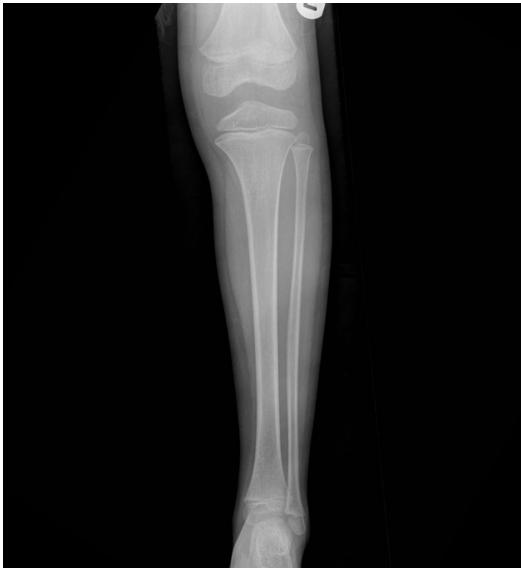

X-ray ap lat closed ,distal tibia extra-articular fracture, complete (two cortex), no articulation involvement, spiral (if two views appear broken), oblique (if one view) Oblique fracture, slight gapping (should be displaced if so), cortex appear normal, minimally displacement, angulation, rotation.